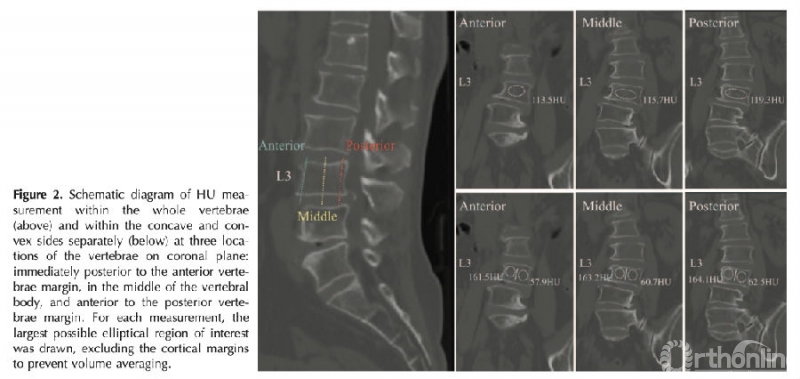

材料与方法:回顾性分析95例退变性侧弯患者的临床及影像学数据,测量腰椎椎体整体松质骨CT值和椎体凸侧和凹侧松质骨CT值。测量方法:选择椎体前皮质骨后方2mm、椎体中部、椎体后皮质骨前方2mm三个层面,上述三个层面测量值的平均值为最终椎体CT值。

图注:退变性侧弯患者椎体CT值测量示意图